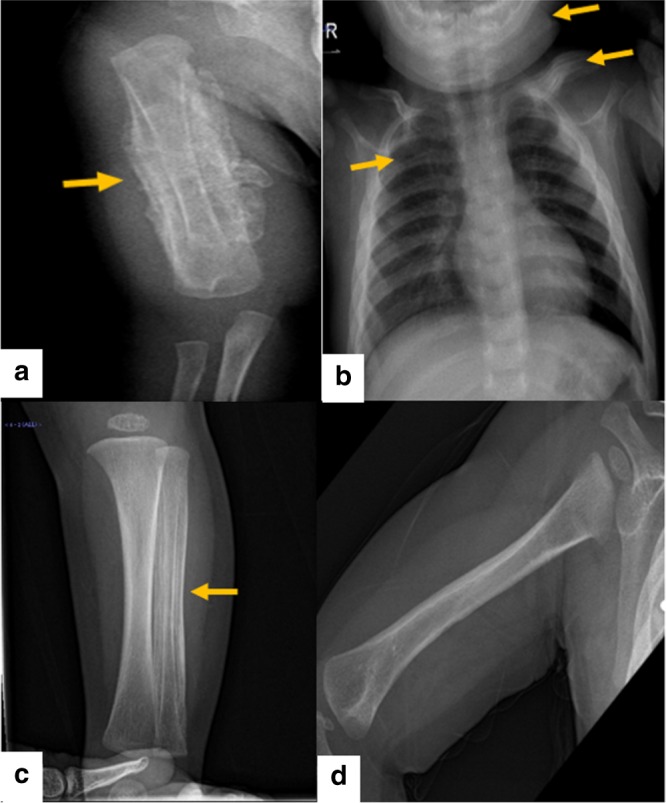

对右臂进行 X 光检查,显示沿右肱骨的整个骨干骨膜反应旺盛(图 1a)。 进一步评估包括 X 线骨骼检查,显示一侧肩胛骨、一根腓骨、下颌骨和许多肋骨有明显的骨膜反应(图 1b)。 根据临床和放射学检查结果,诊断为 ICH。 尽管德托尼-卡菲病可能具有短暂性,但开始使用吲哚美辛(每天 5mg/kg)治疗,并且病变在几个月内有效消失,正如后续放射学检查所证明的那样(图 1c)。 经过 1 年的随访,患者有效康复,没有骨骼畸形和/或升高的炎症标志物。 他仍在服用低剂量的消炎痛(每天 1mg/kg)。

患者的射线照相检查。 a 沿右肱骨整个轴的骨膜反应。 b 沿左锁骨、肋骨和下颌骨的骨膜反应。 c 沿腓骨的骨膜反应。 d 肱骨骨膜有效消退